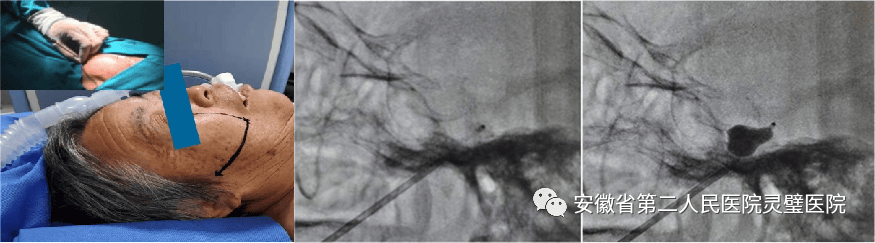

一、颅脑创伤个体化精准救治技术

颅脑创伤是神经外科常见病、多发病,近十年来,我们成功诊治了大量重型颅脑损伤患者,尤其在特重型颅脑损伤、原发性脑干伤、弥漫性轴索损伤等方面积累了丰富的经验,并形成了以“神经多模态监测、亚低温治疗、镇静镇痛、大骨瓣减压以及精准化脑保护”等核心技术为特色的一体化标准化救治方案,重型颅脑创伤患者死亡率逐年降低,达到国内一流水平。

硬膜下血肿、脑挫裂伤术前和术后 颅内压监测

球囊压迫治疗三叉神经痛